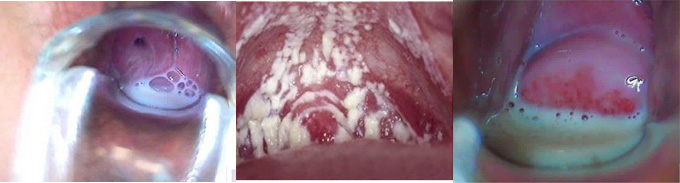

阴道炎图片

阴道炎是女性朋友中非常常见的一类妇科炎症,严重困扰着广大患者的身心健康,阴道炎根据不同的病因又分为多种不同的类型,那么不同类型的阴道炎各自有什么症状呢?阴道炎图片是什么样的?

阴道炎症状图

1、霉菌性阴道炎:白带增多,呈凝乳状或为片块状,阴道及阴道前庭粘膜高度水肿,覆有白色凝乳状薄膜,呈点状或片状分布,严重的患者小阴唇肿胀粘连常伴有外阴及阴道灼热疫痒,有些患者还伴有尿频、尿急、尿痛等症。

2、细菌性阴道炎:此病患者临床约有10-50%无症状,有症状者典型临床症状为阴道异常分泌物明显增多,呈稀薄均质状或稀糊状,为灰白色、灰黄色或乳黄色,带有特殊的鱼腥臭味。(推荐阅读:治疗阴道炎多久不能同房)

3、滴虫性阴道炎:白带增多,可为稀薄浆液状,灰黄色或黄绿色,有些患者还混有血性,20%白带中有泡沫。外阴有瘙痒、灼热,性交痛亦常见,感染累及尿道口时,可有尿痛、尿急,甚至出现血尿的现象。

4、非特异性阴道炎:非特异性阴道炎常见症状为阴道分泌物增多,呈脓性,浆液性,严重时分泌物有臭味。由于分泌物刺激尿道口,引起尿频、尿痛,阴道内下坠感,灼热,伴有盆腔不运及全身乏力。(推荐阅读:阴道炎容易引发哪些疾病)